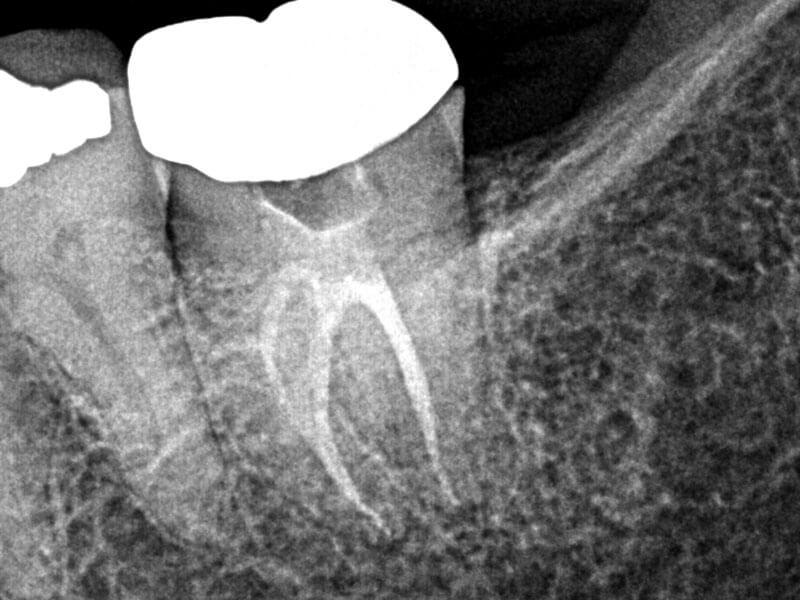

Complex Anatomy

Apical Complex Anatomy with 1 Year Healing Evidence

Michael J. Ribera, DMD, MS

View Case Images